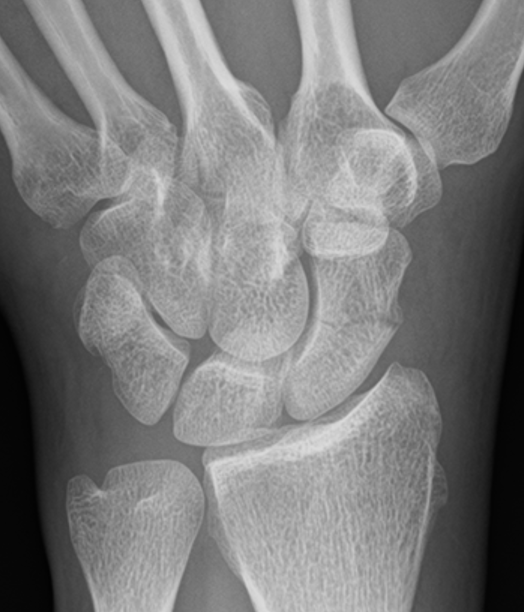

X-ray

5 images

- PA / lateral

- PA in 45° oblique pronation / PA 45o oblique supination

- PA in ulna deviation

CT

Indication: any potential displacement

Scaphoid waist fracture 1 mm displaced

Scaphoid fracture with significant displacement

Scaphoid proximal pole fracture